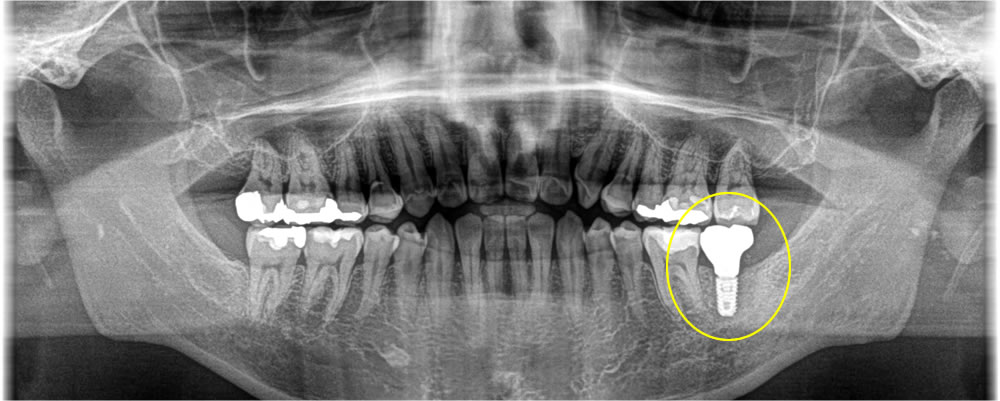

歯根破折のため、骨の欠損範囲が大きく、抜歯後半年ほど時間を置いてからインプラント埋入のオペをしました。インプラント埋入と同時に骨造成(骨を増やす処置)も行いました。

上部構造の装着・治療完了

インプラントと顎骨の結合期間を経て、製作した上部構造を装着。最終的な咬み合わせを調整して治療完了となりました。